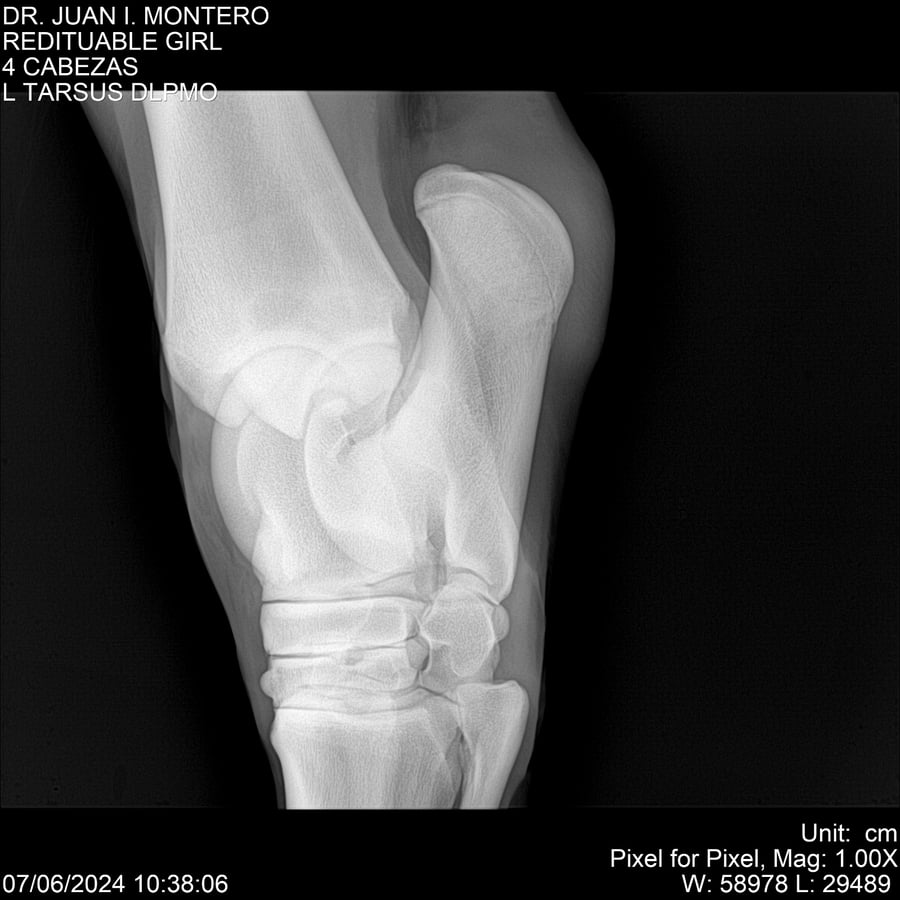

LOTE 19, REDITUABLE GIRL Lote Anterior Volver al remate Lote Siguiente Ficha Contacto Montevideo - Ficha del Lote Identificador: #281096 Categoría: Yeguarizos Montevideo - 79 Visualizaciones ClicData Contacto Empresa: Abelenda N. R., Walter Hugo Nombre*: Teléfono* : E-mail* : Mensaje Enviar Registrese gratis Este contenido Exclusivo está disponible sólo para usuarios registrados Ingresar